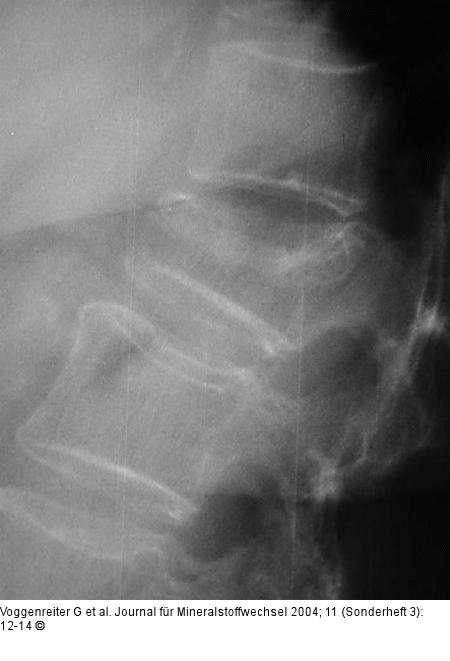

Abbildung 2a-c: LWK1-Fraktur 67jährige Patienten mit einer 4 Wochen alten LWK1-Fraktur und ausgeprägter Schmerzsymptomatik. In der TIRM-Sequenz des MRT erkennt man eine deutliche Signalanhebung in LWK1. |

Abbildung 2a-c: LWK1-Fraktur

67jährige Patienten mit einer 4 Wochen alten LWK1-Fraktur und ausgeprägter Schmerzsymptomatik. In der TIRM-Sequenz des MRT erkennt man eine deutliche Signalanhebung in LWK1. |